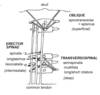

What is the special innervation of trapeizus muscle?

Innervated by CN XI